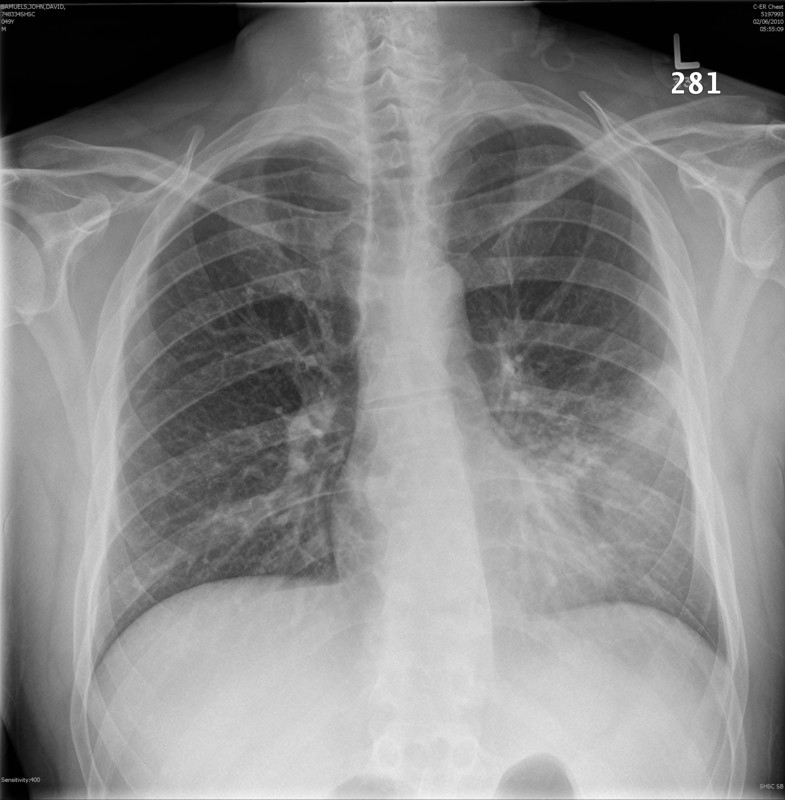

Pneumonia is an illness of lungs causing by virus or inflammatory. It’s mostly seen in older people and children. It mostly starts with flu symptoms and develop symptoms like high fever and cough. Also green mucus starts to come from lungs. Chest pain starts and worsen when patient takes deep breath. Also muscle pain and diarrhea like symptoms are possible through the illness. Diagnose of pneumonia is possible by physical exam or discussion about symptoms. A doctor can easily diagnose pneumonia with coarse breathing and rumblings coming from a stethoscope on chest. How many causes of pneumonia are there?